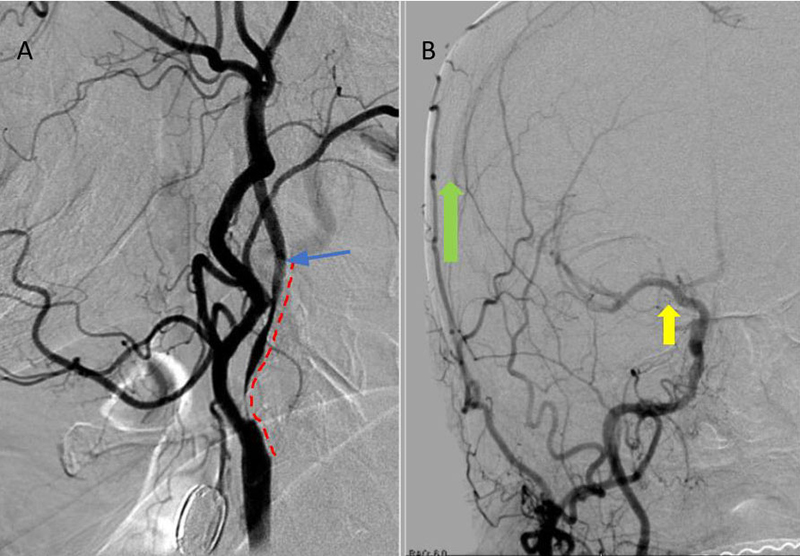

Catheter cerebral angiography was then performed which demonstrated the 99% stenosis with distal vascular collapse and extension of the plaque superiorly into the mid third of the cervical right ICA (Figure 4). Interrogation for collaterals from the left ICA and posterior circulations demonstrated very small and minimal contributions from the anterior communicating artery and posterior communicating artery of the Circle of Willis.

Figure 4. A) DS Angiogram demonstrates severity and extent of plaque to C2-3 level (blue). B) And marked delay of ICA perfusion (yellow) relative to ECA branches (green).